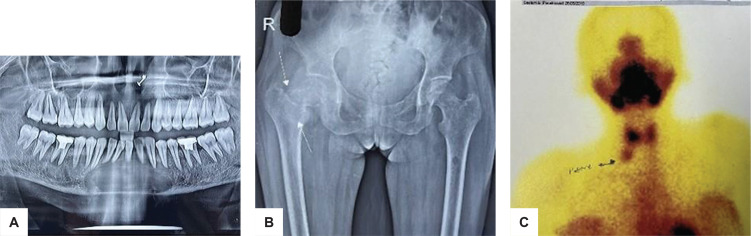

Typically, primary hyperparathyroidism (PHPT) develops as a result of multiglandular hyperplasia, parathyroid cancer, or parathyroid adenoma. Patients usually present with skeletal manifestations such as low-trauma fractures. Osteitis fibrosa cystica (OFC) is a classic yet rare skeletal manifestation of advanced PHPT currently reported in less than 2% of patients. We present a case of a 29-year-old Indian female who presented with a femur fracture and mandibular OFC 20 days after delivery. The painless mandibular swelling gradually progressed from the third month of pregnancy. The biochemical and radiological investigations were indicative of PHPT-associated OFC. After the excision of the three-and-a-half parathyroid gland, histology revealed benign cystic adenomas and hyperplasia. Based on the associated clinical manifestations, OFC was suspected. Clinical exome sequencing revealed CDC73(+) c.687_688dupAG heterogenous pathogenic autosomal dominant mutation. Undiagnosed PHPT in mothers during pregnancy led to neonatal hypocalcaemic convulsions. With adequate supplementation, the infant recovered completely from transient congenital hypoparathyroidism. OFC is an important diagnosis to consider in a young patient with swelling of the neck and jaw. Simultaneous high levels of PTH and serum calcium should raise a high index of suspicion for OFC. Parathyroidectomy helps manage the biochemical abnormalities and causes regression of the jaw mass that causes facial disfigurement and attenuates the declining BMD. Children born to mothers with PHPT should be evaluated for neonatal hypoparathyroidism and supplemented appropriately to reduce the risk of hypocalcaemic manifestations that can be life-threatening. If the CDC73 mutation is detected, the offspring should be monitored for signs of PHPT due to the high probability of inheritance and parathyroid malignancy.